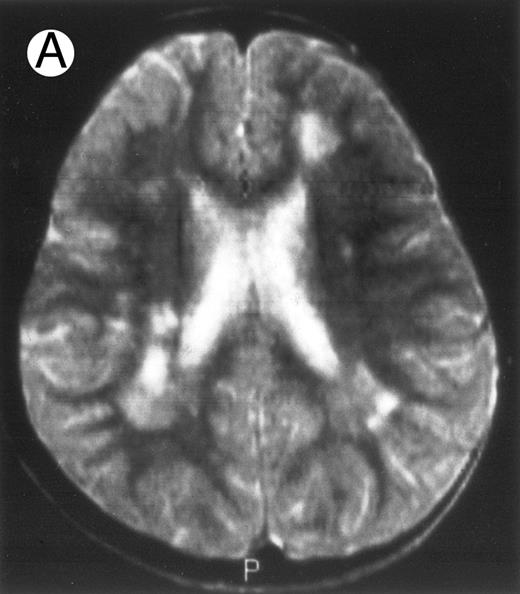

Among the nine children with initial neurological symptoms, seizures were the most frequent initial symptom in the youngest patients, whereas ataxia was found in the two oldest patients (46 and 58 months old, respectively) (Table 1). All nine patients had the same CSF abnormalities as patients with meningitis only. Eight of these nine patients had a neuroradiological study performed at the time of their first neurological symptoms (Table 1). The two most frequent lesions were focal necrosis with parenchymal volume loss and atrophy (Fig 2A and C) and white matter abnormalities (Fig 2B). Several small focal lesions with hypersignal at MR imaging that enhanced after administration of gadopentate dimeglumine (or contrast on CT scan) were also observed in two cases.

Three different aspects of brain imaging in HLH patients. (A) CT scan of a 3-month-old baby showing a large subdural effusion, several necrotic areas and hypodensities of the white matter. (B) Brain magnetic resonance of a 14-month-old boy showing large confluent areas of hypersignal in T2-weighted images. (C) Large symmetrical necrotic areas of cerebellar white matter in a 41/2-year-old girl (MRI).